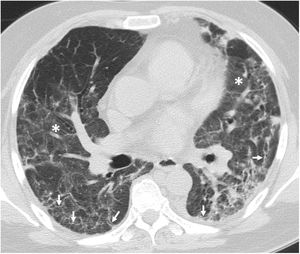

Radiological examples of long-term post-COVID-19 progressionA significant percentage of patients with SARS-CoV-2 pneumonia have radiological abnormalities on the follow-up chest X-ray one month after hospital discharge. In these patients we generally recommend/perform a chest CT without intravenous contrast. In our experience, the severity of the clinical picture usually implies a greater radiological involvement of the lung parenchyma after hospital discharge and a slow favourable response on imaging tests (Fig. 7), especially in patients who required prolonged ICU stays. We do not yet know how much time is needed to establish that the residual radiological findings are stable and definitive. However, some patients with mild or moderate pneumonia may achieve complete resolution of the radiological findings in the first months after discharge (Fig. 8). Ground-glass opacities are among the imaging abnormalities that tend to resolve earlier, while subpleural bands, bronchial dilation and subpleural interstitial involvement usually follow a favourable course that progresses slowly (Figs. 9 and 10). There is, therefore, great variability among patients in the time it takes for residual post-COVID-19 radiological findings to resolve or stabilise. The severity of the clinical picture is probably the most determining factor.

Example of poor radiological outcome in a 62-year-old male patient who required hospital admission due to SARS-CoV-2 infection and invasive mechanical ventilation for 12 days. After 90 days in hospital, the patient was discharged requiring long-term home oxygen therapy and needing rehabilitation. A–C) Chest X-rays corresponding to days 10 (A), 17 (B) and 55 (C) after the onset of symptoms showing extensive persistent bilateral opacities, which are beginning to resolve by the end of the hospital stay. Note the appearance of areas of lower density in the lung bases in relation to pneumatoceles (C, arrows). D–F) Chest computed tomography (CT) images 60 days after the onset of symptoms, in which extensive bilateral fibrotic lesions in the form of subpleural bands and bronchial dilation can be seen, in addition to peripheral air cysts compatible with pneumatoceles (arrows) in the right middle lobe and both lower lobes. One of the lesions in the right lower lobe is in contact with the pleural space, causing a hydropneumothorax (D and F, asterisks). G–I) Chest CT images 90 days after the onset of symptoms, showing a slight improvement in the fibrotic lesions but slightly more growth of the pneumatoceles in the right middle lobe and left lower lobe (arrows). Note the incidental detection of an eccentric filling defect in the left lower lobe artery (I, asterisk) consistent with a subacute pulmonary embolism.